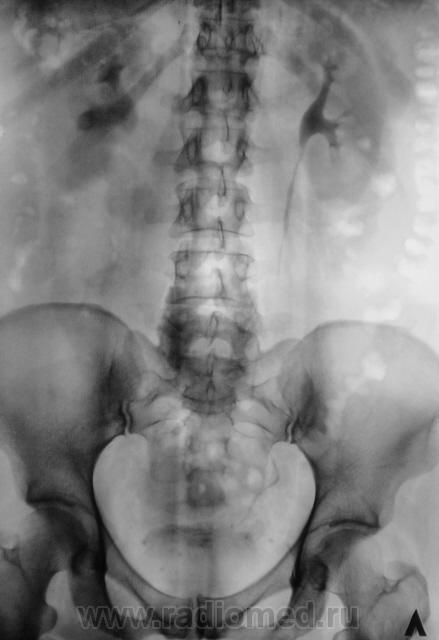

После введения контрастного вещества урограммы произведены на 7 и 15 минутах.

В проекции среднего сегмента правой почки тень конкремента. Отсутствие признаков расширения собрательной системы правой почки.

Да, контраст "покрыл" тень рентгеноположительного конкремента.

А мне этот конкремент, при всей его "рентгеноположительности", видится дефектом наполнения чашки, контрастированной ещё более "рентгеноположительным" контрастом)).

Ещё более отчетливо это может было бы увидеть на прицельной рентгенограмме почки либо томограмме её.